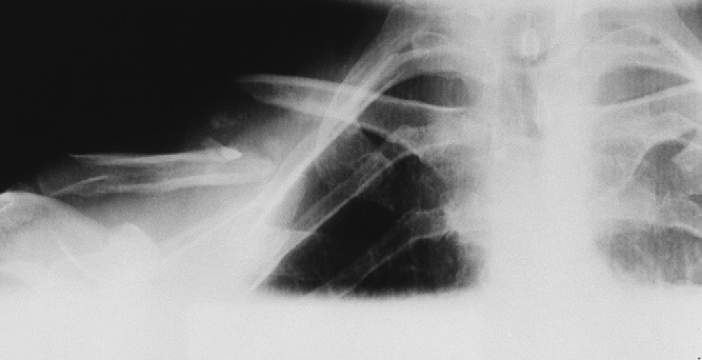

Clavicle fracture